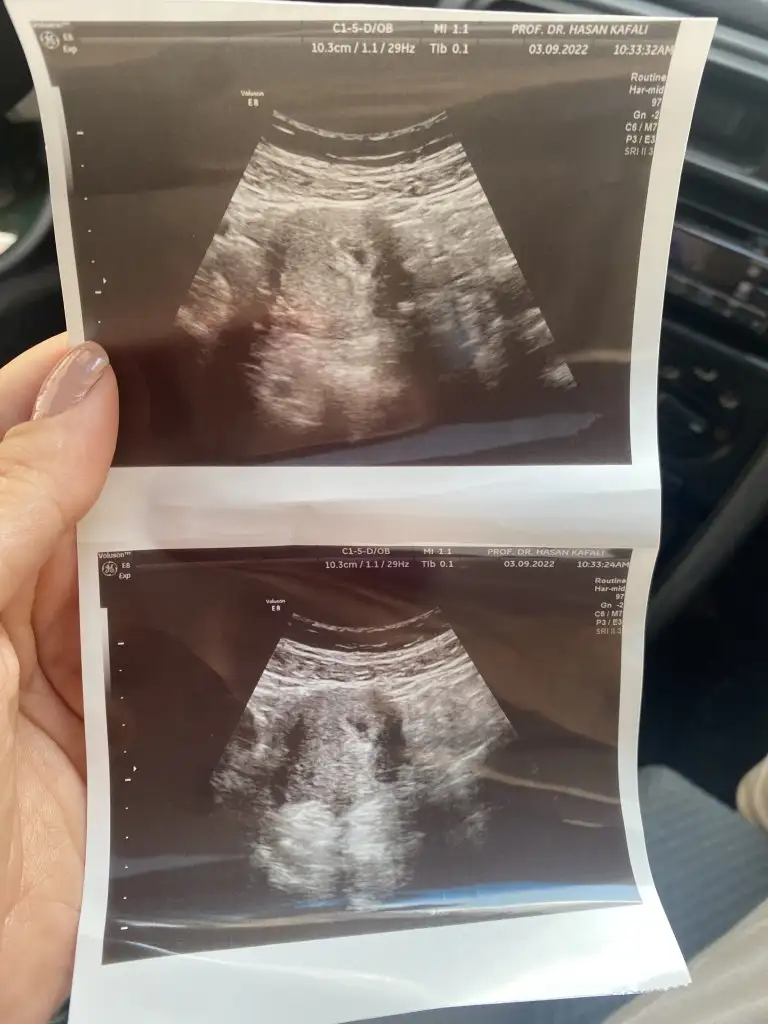

Ya ben erken gittiğimi de düşünüyorum ama yine iyi keseyi gördü . Haftaya bidaha gidicem bakalım ne der kese de iki bebek çıkar mı sonradan dedim ama çıkmaz yazmış Efolis Efolis hayırlısı artık ☺️Buna da şükür.

Tek kese gorunduyse bubdan sonra tek kese uzerinden ilerlersiniz cancazim ikiz bebekse bile tek kesede yani tek yumurta ikizi olurlar onu bilmek icinde erken suan 🥰

Siz ne görüyorsunuz fotoğrafta anlamıyorum ki hiç bişe 👶

Ust fotoda iki kese gorunuyor gerçekten kucukler ama 😍 alt fotoda goruntuden kaynakli teki gorunuyor alttaki kese dedigim yapi cizgiler icinde kaybolmus gini görünüyor biraz buyuyunce belli olacaktir tabiki ama insan haliyle merak ediyor

İki mi görüyorsunuz 🤲☺️ ben fasülye gibi bi tek kese gördüm . Ama doktor hiç iki demedi ya haftaya net bakarız dedi ama sonuçta bi kese var yani diyo . Sağlıklı olacaklarsa olsun iki isterim gerçekten 🌸👶

🥰 Allah bize bagislasin hayırlısıyla sımsıkı tutunsun yavrularimiz insallah ikiside seninledir daha dun sabah bana da kesenin biri bos demisti ama oyle değil kocaman yavrum gorunuyordu kesenin icinde 😍